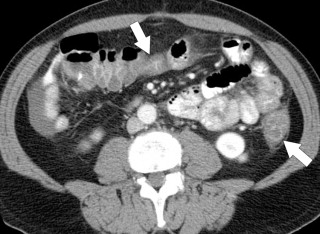

The presence and extent of disease are more readily evaluated by CT than by contrast enema, whose features also mirror the clinical disease. These include bowel wall thickening and luminal narrowing with a variable amount of pericolonic edema and mesenteric vascular hyperemia ( Fig. 5-13 ). The degree of inflammation may be reflected by 18 F-fluorodeoxyglucose (FDG) uptake at PET imaging ( Fig. 5-13 ). Mural stratification or double-halo sign, which is common with an acute presentation, is a nonspecific sign for inflammatory bowel disease representing hyperemic mucosa and serosa with intervening submucosal edema ( Fig. 5-14 ). If the acute disease worsens, the mucosa becomes progressively thickened and inflamed ( Fig. 5-15 ), which can ultimately lead to a toxic megacolon, whose CT features include a distended colon with profusely thickened mucosal tissue, sometimes referred to as an “accordion pattern” (see Fig. 5-52 ).

Figure 5-14, Axial contrast-enhanced CT in a 45-year-old man with sigmoid mural stratification ( arrow ) due to acute ulcerative colitis.